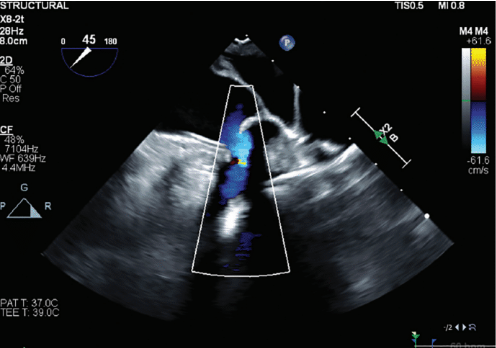

A 78-year-old woman was referred to Northside Hospital Heart Institute for possible LAAC. She had a history of coronary artery bypass grafting (CABG) over 5 years ago, permanent AF with history of atrioventricular node ablation, and permanent pacemaker implantation. Her CHA2DS2-VASc score was 5 due to hypertension, age >75, diabetes, and vascular disease. This placed her at high risk for stroke, but her cardiologist deemed her not to be a good candidate for long-term oral anticoagulation due to intracranial hemorrhage with multiple falls. An operative report of the CABG was obtained, but the report showed only 3-vessel bypass with no report of LAA ligation. Computed tomography (CT) with contrast of the heart was also obtained, which is standard practice for many of our LAAC procedures, especially for patients who have had prior cardiac surgeries. There was a 5.3-mm leak noted at the surgical closure at the base of the LAA (Figure 1). This leak was too large to close with endovascular coils, and there was concern about using an endovascular plug due to length of the leak and possible effects of radial forces over time in the channel. The Amplatzer Amulet device was chosen for this case, with the plan to place the lobe inside the LAA and place the disc covering the channel with forces after closure to be axial in direction. The procedure was performed under general anesthesia and transesophageal echocardiography (TEE) imaging. LAAC procedures at Northside Hospital Heart Institute are usually performed using TEE guidance only, with no use of contrast, since our noninvasive physicians (Drs John Ricketts and Colin O’Brian) provide imaging for transseptal puncture, device deployment, and post-imaging for any leaks, including 3D TEE at every step when needed. Due to the unusual nature of this anatomy, we performed contrast fluoroscopy of the LAA. Figures 2A and 2B show the pre-implant and periprocedural TEE images. Figure 3 shows the contrast injection through the 12 French Torque Vue 45-degree Amulet delivery sheath (Abbott) and the Glidewire (Terumo Interventional Systems) in the LAA. The placement was primarily guided by TEE imaging. The smallest size (16 mm) Amulet device was chosen for closure. Figure 4 demonstrates placement under fluoroscopy. Figures 5A and 5B demonstrate closure using TEE imaging. Post procedure, the patient was placed on aspirin and clopidogrel for 3 months. Once adequate seal is confirmed at 3 months, the goal is for the patient to switch to aspirin (81 mg).